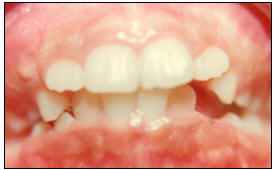

Fig. 2.-

(16-enero-1985) Vista intraoral, se puede observar

inclinación distal de los incisivos laterales

superiores, posiblemente ocasionado por el proceso

eruptivo de los caninos, también se puede ver el

ligero apiñamiento de los incisivos inferiores |